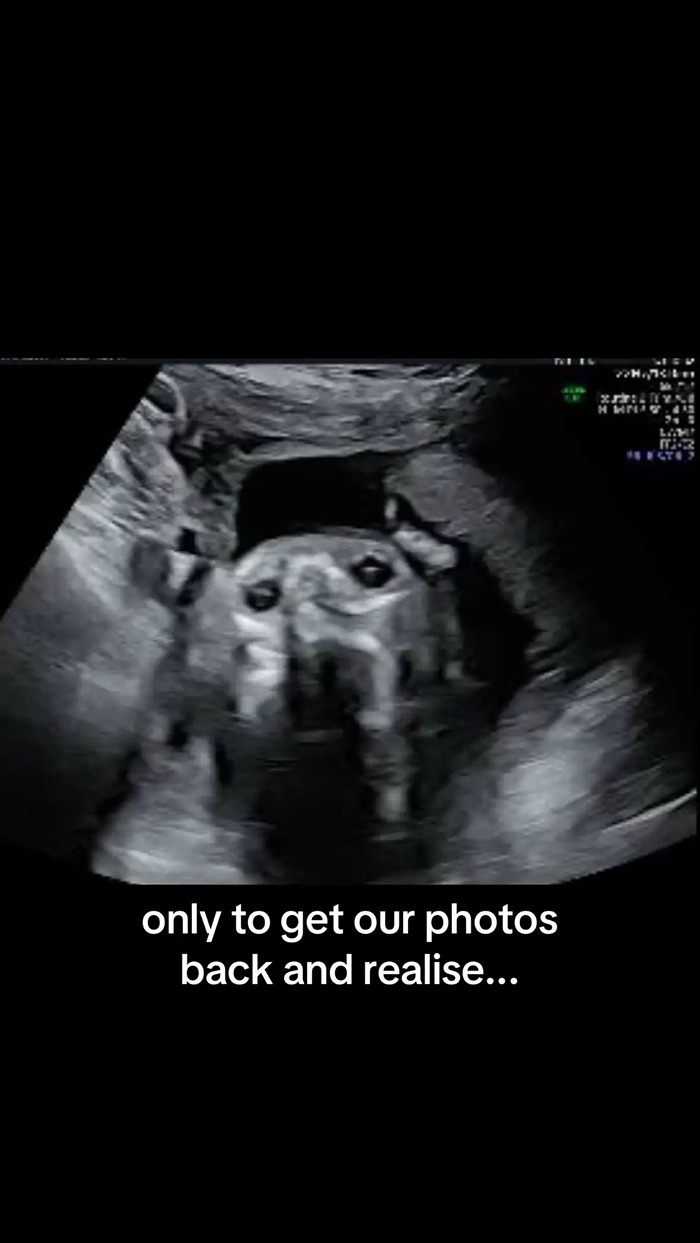

Inês Egner, an influencer and soon-to-be mother from Portugal, couldn’t believe her eyes when her 20-week anatomy scan revealed something unexpected, and hilarious.

Instead of her baby, the machine showed what appeared to be the face of her dog, Goulash, staring back at her.

“We were so excited for our anatomy scan,” Egner wrote across the first slide of her post. “Only to get our photos back and realise our son looks remarkably like our dog!”

As for what created the strange, dog-like image. Egner explained to her viewers that it was most likely the result of a weird angle.

“They were checking from the angle of his chin, checking up his nostrils and his eyes,” she said.